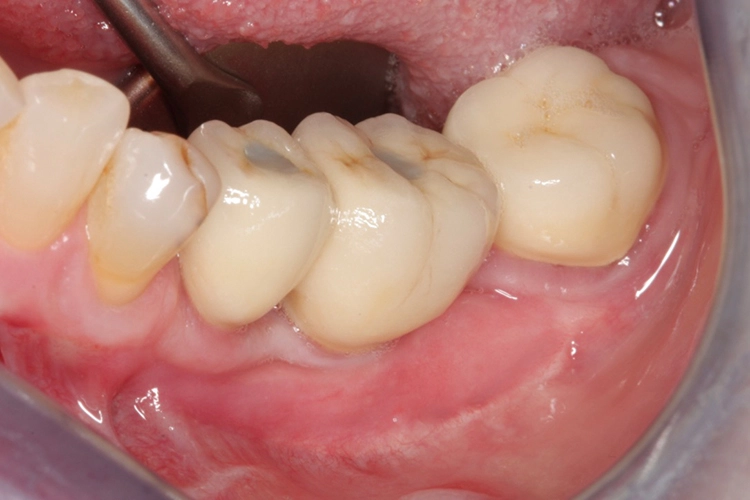

Die Kronen wurden auf den Implantaten verschraubt, um einer durch Befestigungszement induzierten Periimplantitis sicher entgegenzuwirken. Das klinische Abschlussfoto zeigt reizfreies Weichgewebe im periimplantären Bereich sowie eine ausreichende keratinisierte Mukosamanschette periimplantär (Abb. 20).